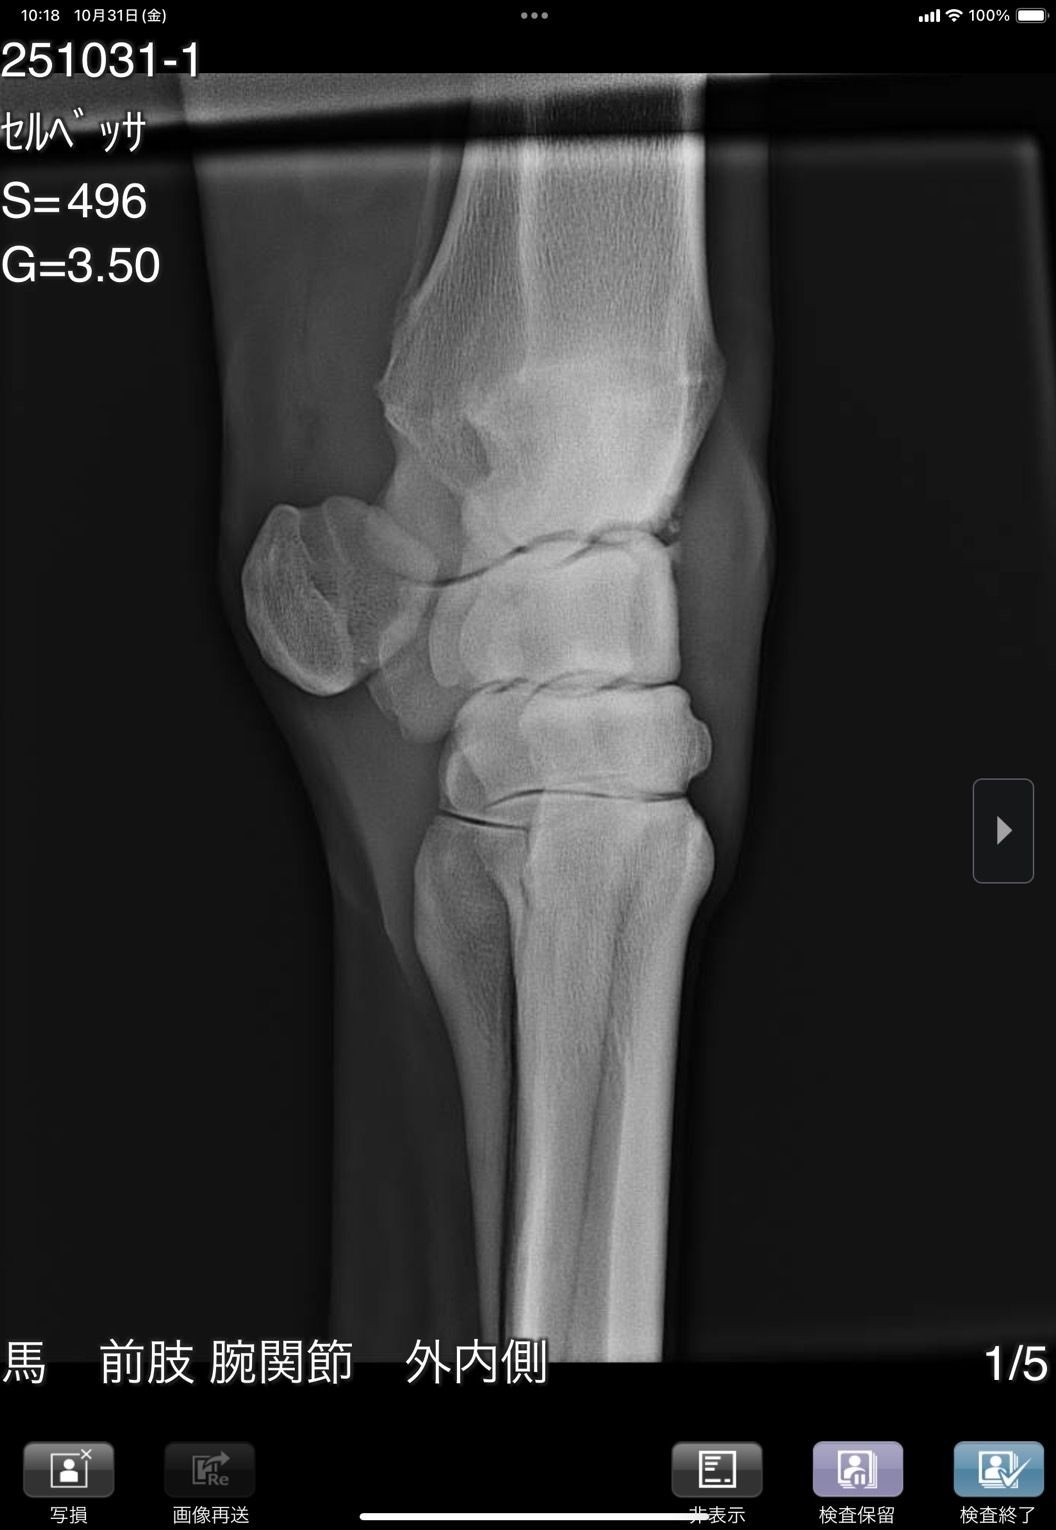

前肢が外向しているためか1歳秋の育成段階で右前に骨瘤ができ、中々固まらずに育成も遅れ、デビューは3歳4月となりました。デビュー後は4ヶ月で6戦を消化し比較的順調に出走できましたが、8/28の出走後にC3級への降級を狙って休養へ。帰厩に向けて乗りこんでいる所でしたが、10/31の調教後に右前膝に違和感があり、レントゲン検査を実施した所、骨片の剥離が見られました。その段階では大きな跛行は見られなかったためしばらく様子を見ましたが、速い調教を行うと歩様に違和感が出るため、手術が必要と考えられます。骨片除去手術を行いますと一定期間の休養が必要となるため、この度オークションへの出品とさせて頂きました。骨片除去手術は必要になると思いますが、元々の戦績からすると園田C2級で勝ち負け出来る能力があり、休養中にC3級への降級となりますので、適切な治療と休養をして頂ければ勝負になる可能性は高いと思います。骨折の状況については8/31撮影のレントゲン画像をご確認ください。

※10月31日の調教後に右前膝に違和感があり、レントゲン検査を行った所、骨片の剥離が見られました。